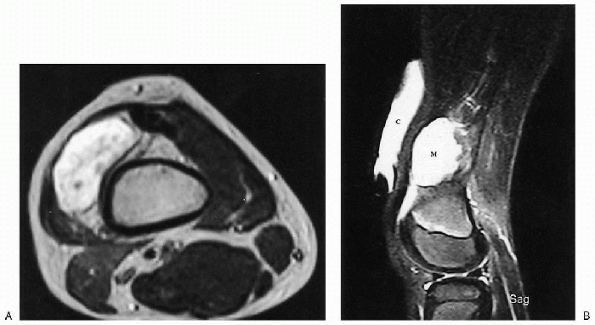

Figure 23-16 Vascular malformation: lymphangioma. (A)

Axial T2-weighted magnetic resonance image of the distal thigh shows a high-signal intensity mass similar to fluid. No vessels or septations are seen within the mass. (B) On sagittal T2-weighted image, a vitamin E capsule (C) is used to mark the site of the palpable mass. Note the high signal of this fluid-filled mass (M). A small suprapatellar effusion, just inferior to the mass, has the same signal intensity. |

nature of vascular anomalies and defining their relationship to

adjacent structures (Fig. 23-16). Ultrasound or color Doppler may also be used.